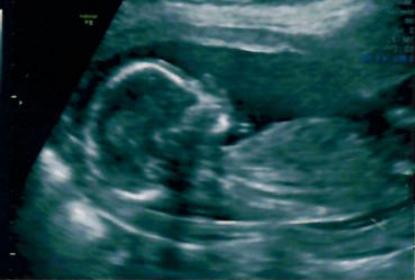

Now I got clear pics of 12W, 16W & 20 W.

16 W imagesAttachment 28068Attachment 28069

20 W imageAttachment 28071

I think girl as I can't see anything on this potty shot xxx

Maybe girl!

hi how do u predict? Bcos in first pic I could see a nub pointing upwards?? Could anyone clarify??